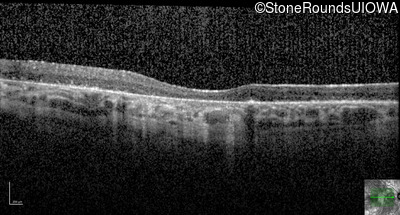

Optical Coherence Tomography - Left - 10/225

Exemplar / OCT Stack